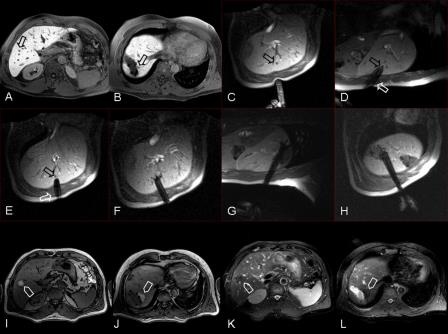

Legende zu den Abbildungen A. - L.

MR geführte Radiofrequenz-Ablation (RFA)

A. Patient mit 2 residuellen Lebermetastasen eines Phäochromozytoms der linken Nebenniere nach stattgehabten atypischen Leberteilresektionen. Der Pfeil markiert eine kleine Metastase in Segment VI

B. Angrenzend an den Resektionsrand zeigt sich die zweite residuelle Metastase in Segment VII

C. Markierung des Zugangsweges zur Metastase in Segment VI mittels aufgelegtem Finger

D. Punktion der Läsion mit der RFA-Sonde. Selbst kleinste Läsionen können präzise getroffen werden

E. Darstellung der RFA-Sonde in der 2 Trajektorie, Bestätigung der korrekten Sondenposition

F. Ausfahren der Schirmchenelektroden

G. Ablation der zweiten Läsion angrenzend an den Resektionsrand im Segment VII in analoger Weise

H. Zwischenzeitlichen Umpositionieren der RFA-Sonde um auch eine suspekte Ausziehung der zweiten Metastase vollständig zu erfassen

I. Kontrollserien (T1 Wichtung): Die therapierte Metastase im Segment VI ist vollständig von einer Koagulationsnekrose (helles Areal) umgeben und somit vollständig ausgeschaltet

J. Vollständige Ablation der Metastase in Segment VII

K. Korrespondierendes Kontrollbild in T2 Wichtung; die Koagulationsnekrose kommt im fettgesättigten T2 Bild als dunkle „hypointense"

Zone zur Darstellung

L. Vollständige Ablation der zweiten Metastase in Segment VII